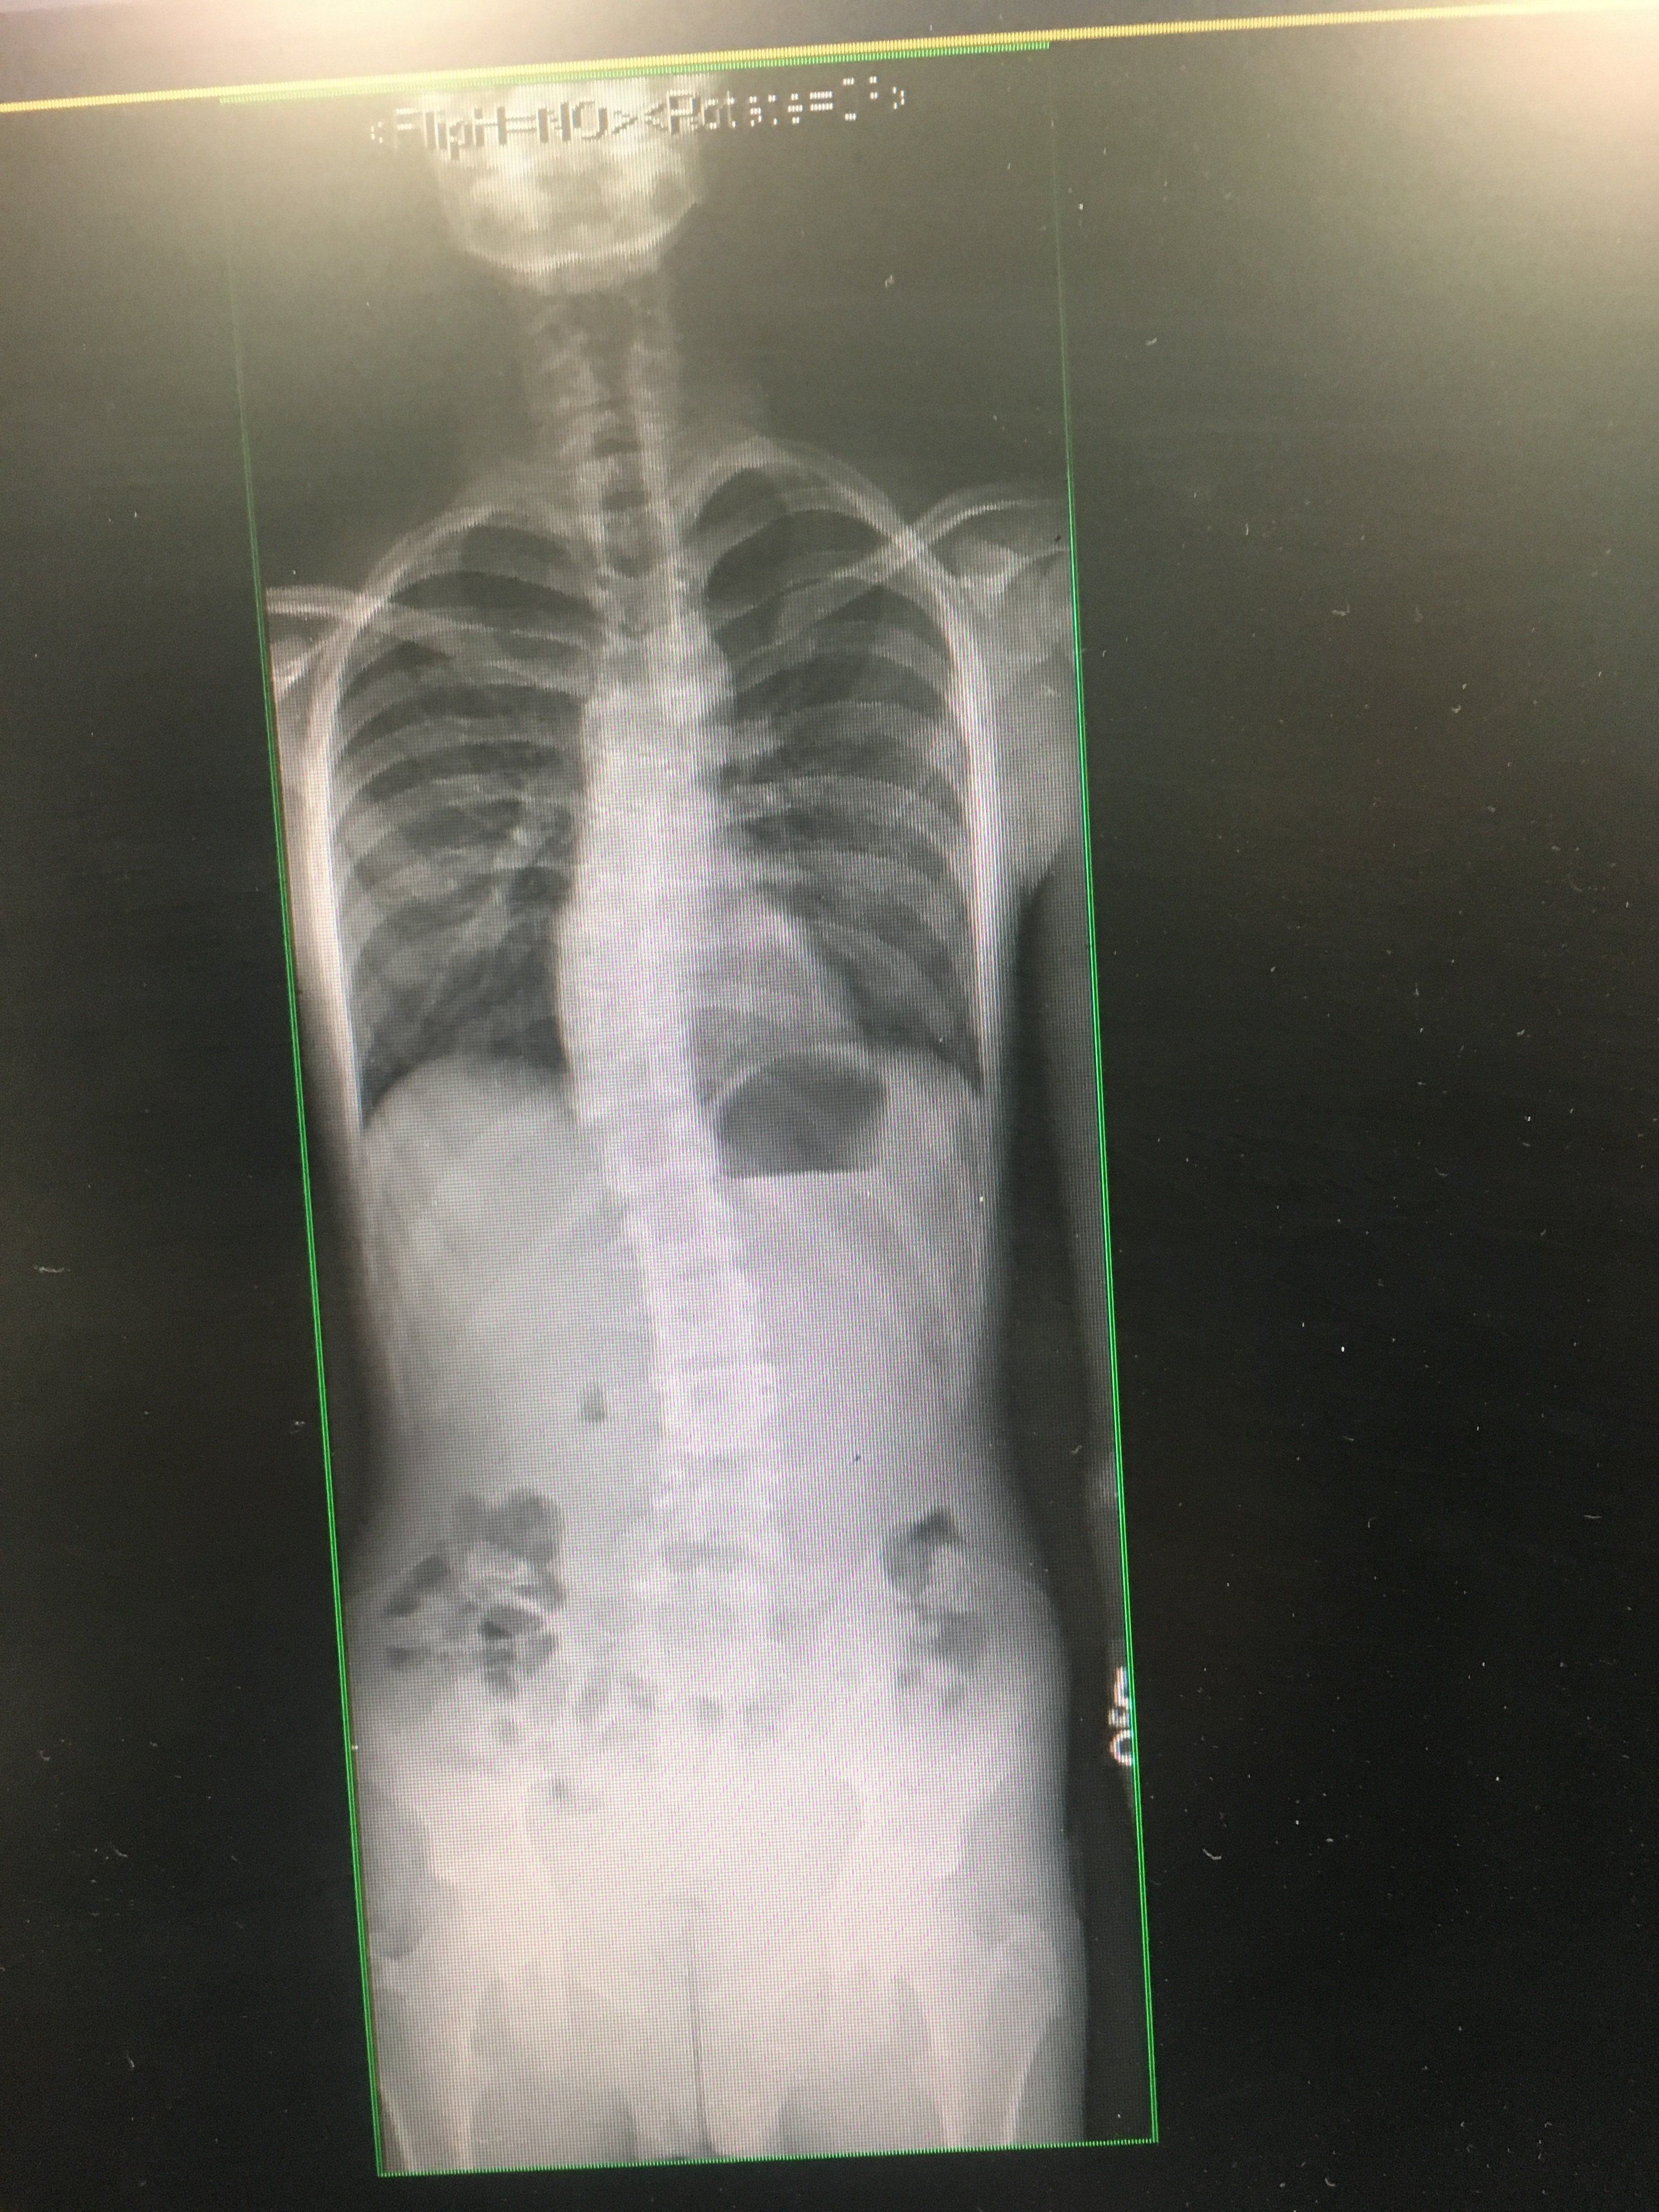

If you ever fee bad fat man just be glad you don’t have scoliosis + stunted spine growth

View attachment 31429

Just look at my traps and ribs jfl :( not to mention shorts asf torso (nigger bodytype) :(

I want my spine surgically lengthened too because it hasn’t grown in two years because of scoliosis surgery.